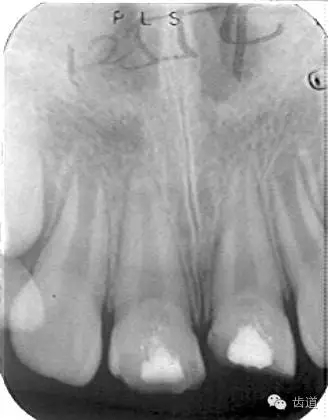

術(shù)后三個月

術(shù)后六個月

術(shù)后兩年